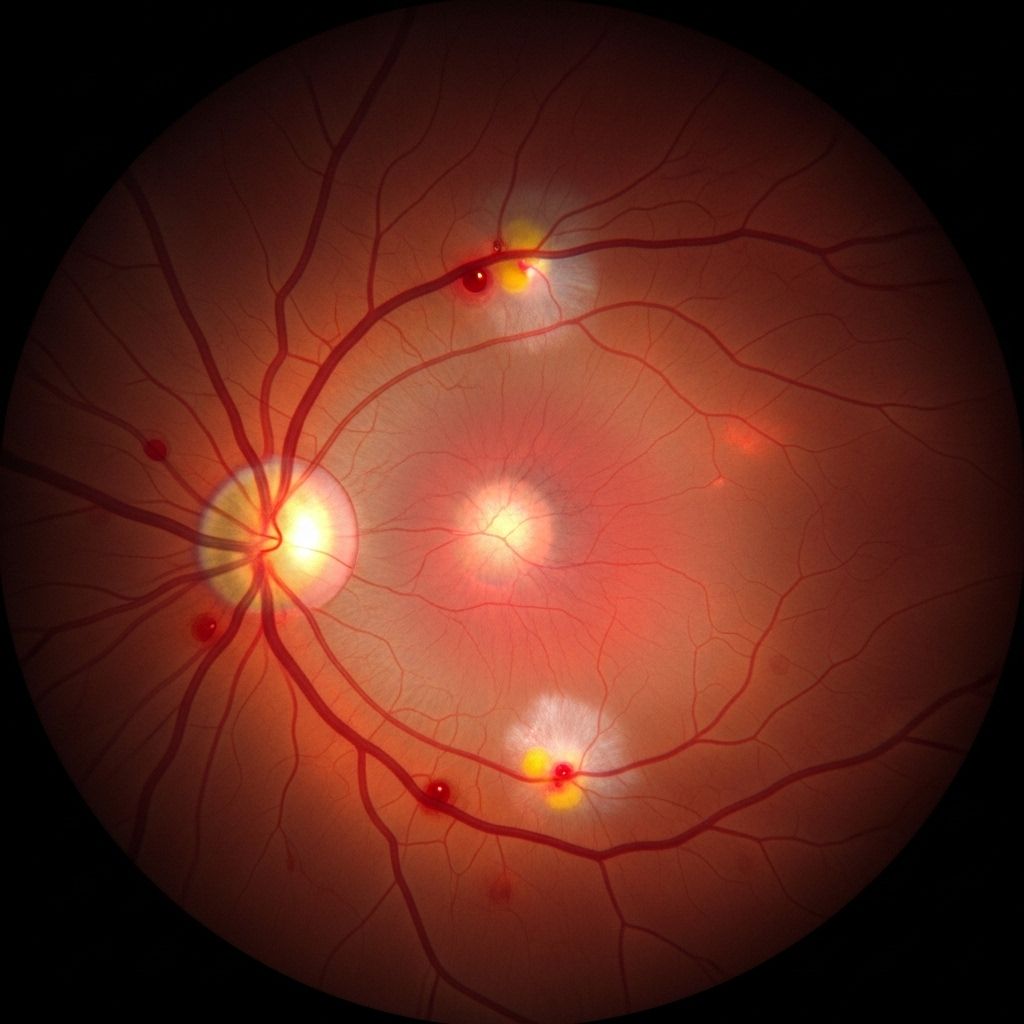

Types of Diabetic Retinopathy

Understanding the types and stages of diabetic retinopathy helps in assessing how risk factors influence disease progression:

- Nonproliferative Diabetic Retinopathy (NPDR): Early stage in which blood vessels in the retina weaken, bulge (microaneurysms), and may leak fluid or blood. NPDR can range from mild to severe, depending on the amount of leakage and swelling.

- Proliferative Diabetic Retinopathy (PDR): Advanced stage where new, abnormal blood vessels proliferate on the retina or into the vitreous. These vessels are fragile and prone to bleeding. Scar tissue from new vessel growth can cause retinal detachment or severe vision loss.

- Macular Edema: Fluid leaking into the macula (the central portion of the retina critical for detailed vision) can cause the macula to swell, leading to central vision loss. Macular edema can occur at any stage but is a crucial cause of vision problems in diabetes.